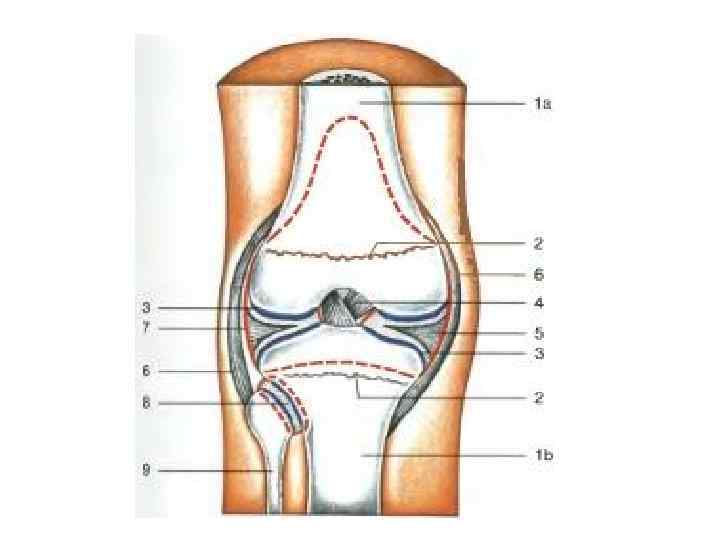

Колінний суглоб (articulatio genus)